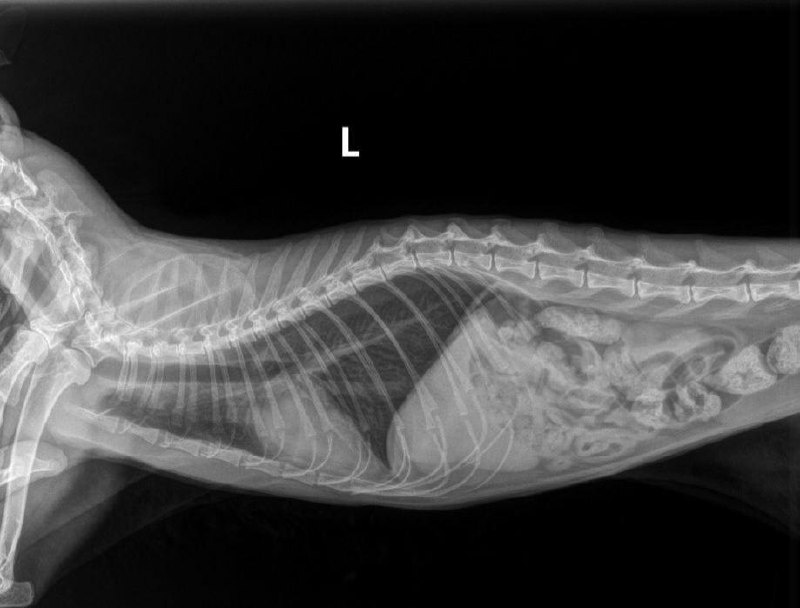

В клинику «ТерраВЕТ» на Советской в критическом состоянии попал котик Перси, которому всего 3 года. У него были признаки отека легких и острого расширения желудка.

У героя нашей истории был кардиогенный отек легких, вызванный врожденными заболеваниями сердца, а также осложненный бронхитом, который врачи выявили на КТ.